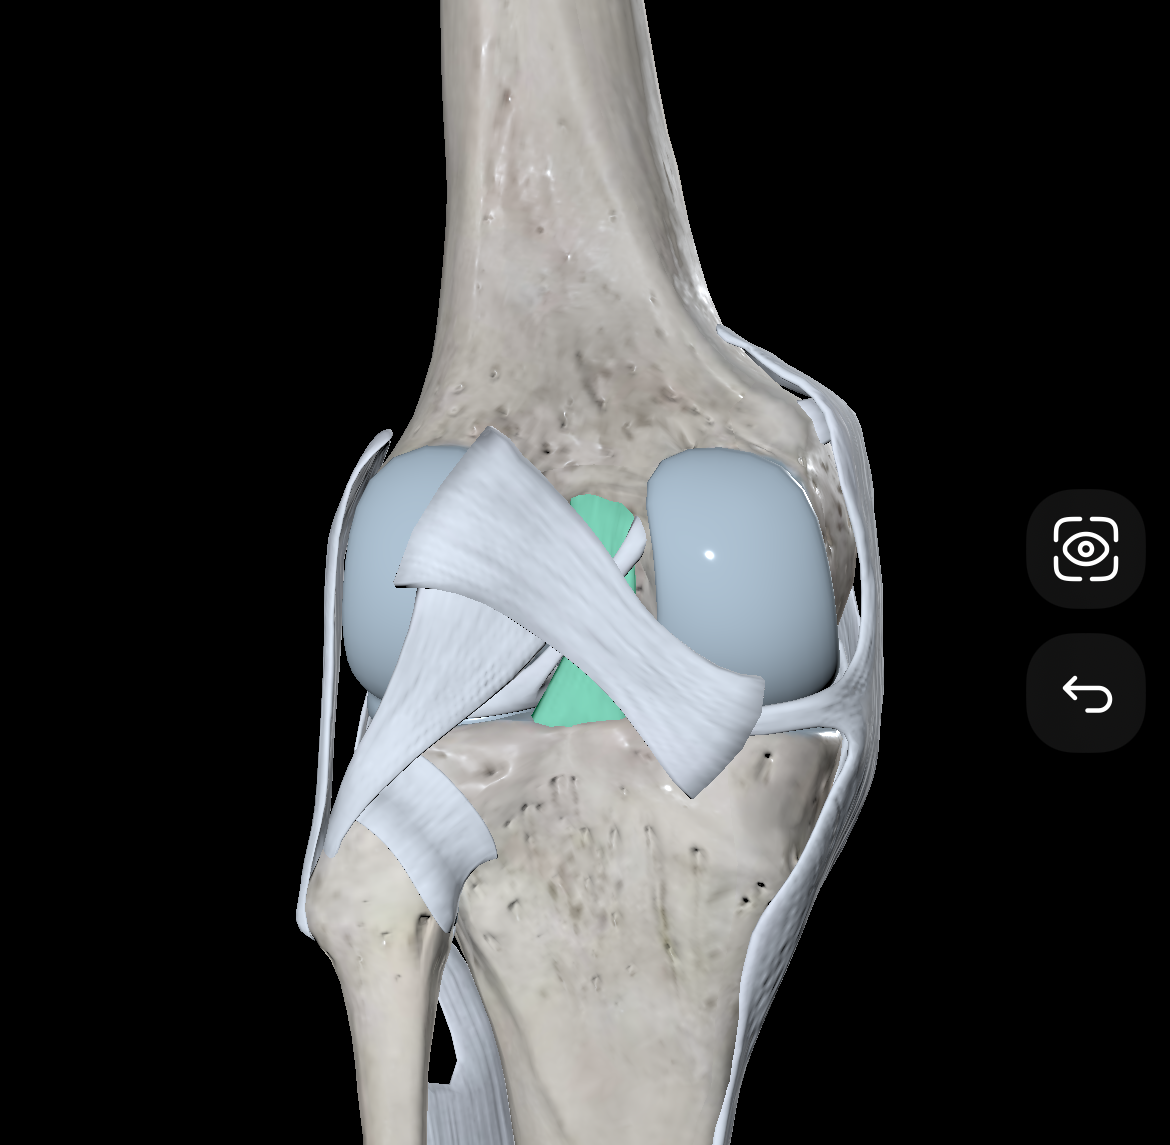

Medial Condyles of the Femur

Lateral Condyles of the Femur

Medial Tibial Condyles

Lateral Tibial Condyles

Anterior Cruciate Ligament

Posterior Cruciate Ligament